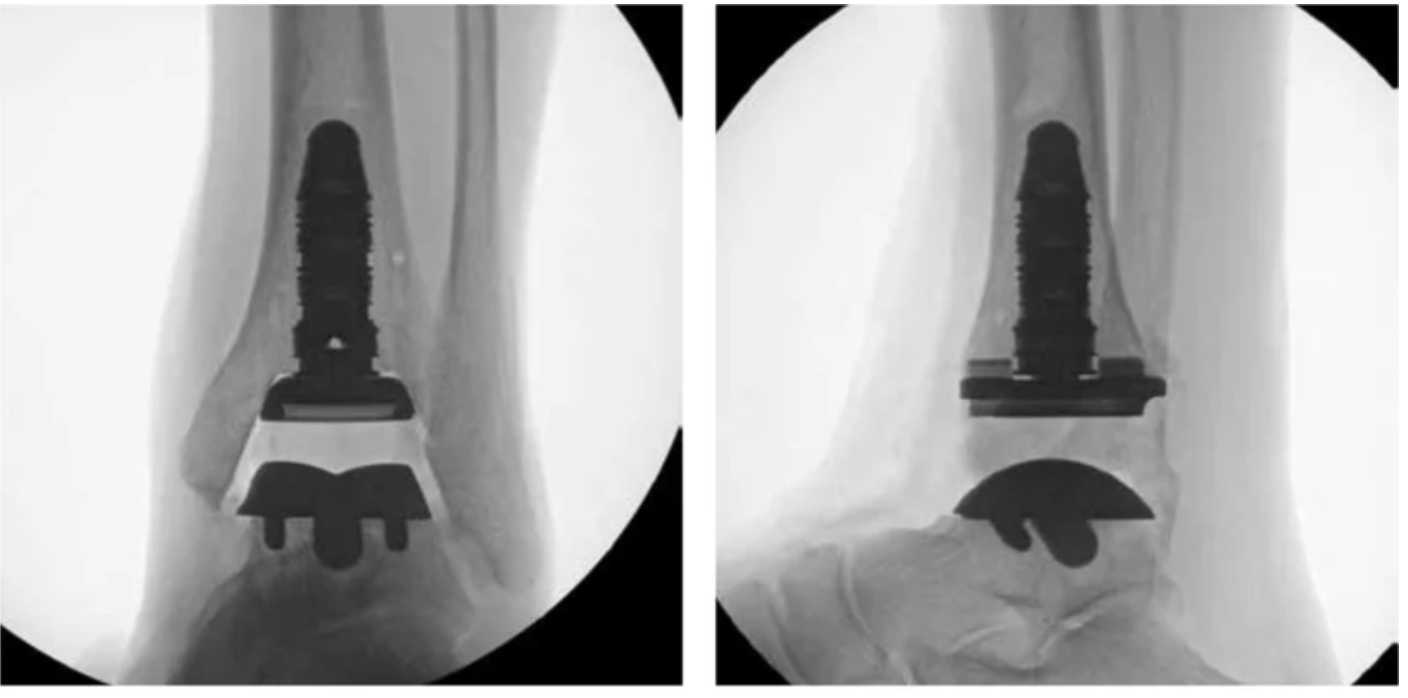

X-ray images of the INBONE II implant Total Ankle Replacement system. Intra-operative anterior-posterior and lateral fluoroscopic images of the ankle with INBONE II implant system. (Image courtesy of Wright Medical Technology, Inc., Memphis, TN, US)

The INBONE II implant’s robust modular stem fixation is particularly well suited to this approach, providing the initial stability needed to walk earlier without compromising implant security.